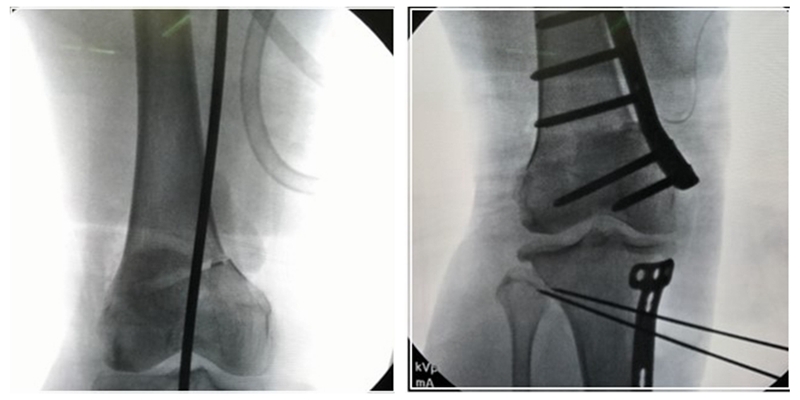

2、手术的顺序

对于手术顺序,提倡先做股骨。当股骨闭合,胫骨开放时,推荐优先做股骨,有利于准确调整下肢力线;当股骨闭合,胫骨闭合,同样推荐先做股骨,不容易发生相应的并发症。但是当出现术前全长片不标准,术前计划不准确时,建议先胫骨,胫骨较容易看关节线。

3、手术的关键

第一侧截骨要把关节线放平;第二侧截骨要达到整体目标力线。

如果术前存在扭转畸形的老年患者(残留扭转,纠正内翻),此时的治疗目标为纠正冠状位力线,这时就要忽略扭转畸形,术中判断要以足踝为标准,不要以髌骨为标准。

术前计划时当胫骨开放较大的情况下,股骨就要截够,为胫骨侧留一些余地。

经典病例